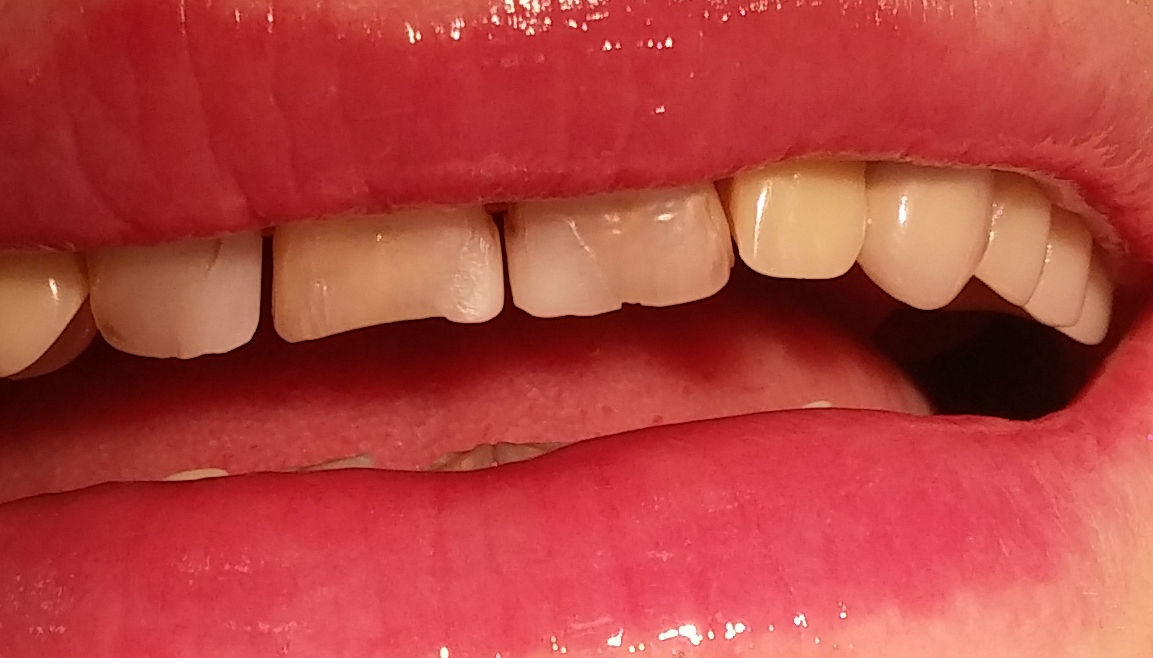

Konkurs sprawdzał umiejętności praktyczne studentów i dotyczył odbudowy zębów w odcinku przednim lub bocznym z użyciem materiałów stomatologicznych Dentsply Sirona.